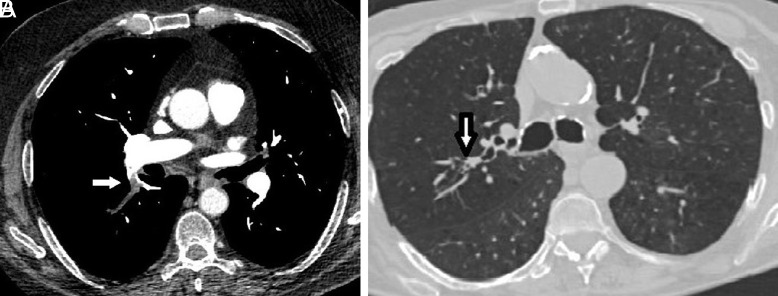

Material and methods: The retrospective study examined 200 participants diagnosed with both COPD and pulmonary embolism. Of these, 100 patients exhibited mucus plugs in the segmental and subsegmental branches of the pulmonary bronchial tree, while the remaining 100 did not, using computed tomography images for diagnosis. Data collection encompassed a comprehensive review of patient records, including medical history and imaging reports, to determine the presence of mucus plugs and the localization of clots in pulmonary embolism cases.

Results: Patients with mucus plugs exhibited a notably longer duration of COPD (P = .021) and a higher mean pulmonary arterial occlusion index (23 vs. 12, P = .001). Moreover, the prevalence of clots in major pulmonary arteries was significantly elevated in the mucus plug group compared to the non-mucus plug group (P < .05). Conversely, patients without mucus plugs displayed a higher incidence of clots in segmental and subsegmental arteries (P < .001). Strong positive correlations existed between mucus plugs in segmental branches and clots in major pulmonary arteries, with moderate to strong correlation coefficients (0.51 to 0.62, P < .05). Additionally, strong negative correlations were observed between mucus plugs in segmental branches and clots in segmental and subsegmental arteries, with correlation coefficients (CC) ranging from -0.74 to -0.76 (P < .05). Similarly, a significant negative correlation was noted between mucus plugs in subsegmental branches and clots in subsegmental arteries (CC: -0.68 and -0.71, P < .05).